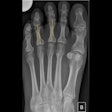

First figures released on imaging of Tokyo Olympics

Radiology swings into action at Tokyo Olympics